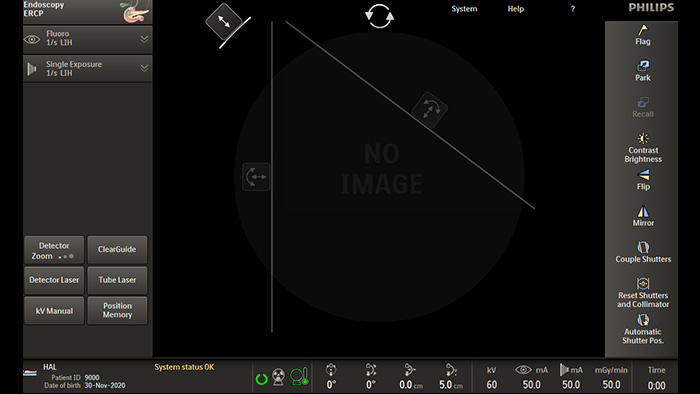

Fluoroscopia pulsada para obtener imágenes de las características anatómicas densas

La fluoroscopia pulsada mejora las imágenes de las características anatómicas densas y complejas para ayudarle en el manejo de la dosis. Puede seleccionar un rango de frecuencias de pulsos de fluoroscopia para reducir la dosis cuando se desee o mejorar la calidad de la imagen según sea necesario.